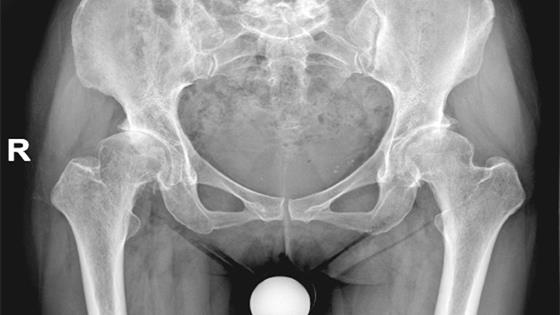

股骨头坏死是最常见的股骨头疾病,而人工股骨头置换术是对于接近塌陷或塌陷变形以及长期疼痛和出现功能障碍的患者所进行的治疗方法。人工股骨头经过不断的完善改进和设计,目前有多种材料的人工股骨可选择。术前需确定患者的心、肺情况及有无糖尿病,才能确定能否进行人工股骨头置换术。

1、股骨头粉碎性骨折、股骨颈骨折复位失败、股骨颈和髋臼骨吸收仍然正常的患者可以进行置换治疗。

2、股骨头良性肿胀和伴有股骨病变性骨折的恶性转移性肿瘤,人工股骨头置换术可缓解患者的疼痛。